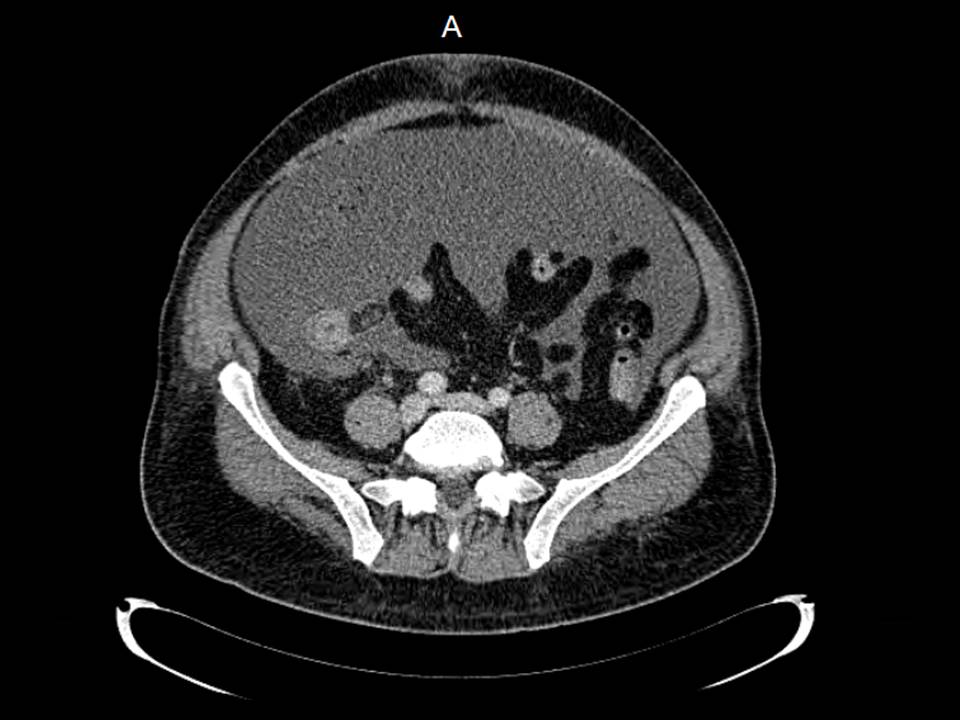

Paciente de 12 años con dolor abdominal. Remitida para estudio de masa intraabdominal.